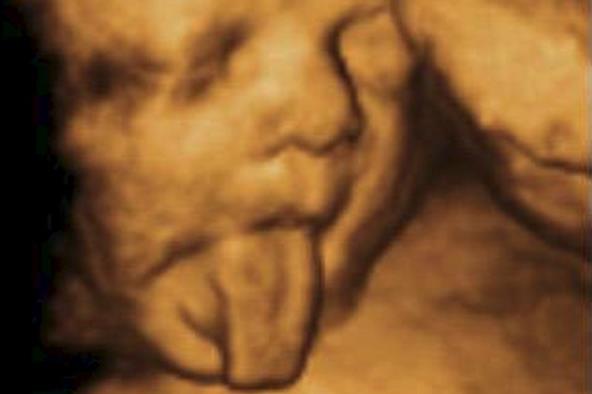

Gotovo svi budući roditelji ne mogu da dočekaju trenutak kada će na učtrazvučnom pregledu prvi put moći da vide svoju bebu, a te fotografije često ostaju uspomena za čitav život.

Ipak, izgleda da mnoge bebe i pre nego što se rode imaju dobar smisao za humor, pa tako često iznenade svoje roditelje.

Ovo su samo neki od najsmešnijih sonograma koji su postali populrani na internetu: